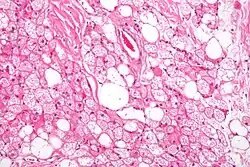

A high power hematoxylin and eosin stained photograph of a hibernoma.

The tumors histologically resemble brown fat. There are four histologic types recognized, but one is the most frequently seen (typical). There is a background of rich vascularity.

1. Lobular type: Variable degrees of differentiation of uniform, round to oval cells with granular eosinophilic cells with prominent borders, alternating with coarsely multivacuolated fat cells (pale cells). There are usually small centrally placed nuclei without pleomorphism. The cells have large cytoplasmic lipid droplets interspersed throughout.[4][5]